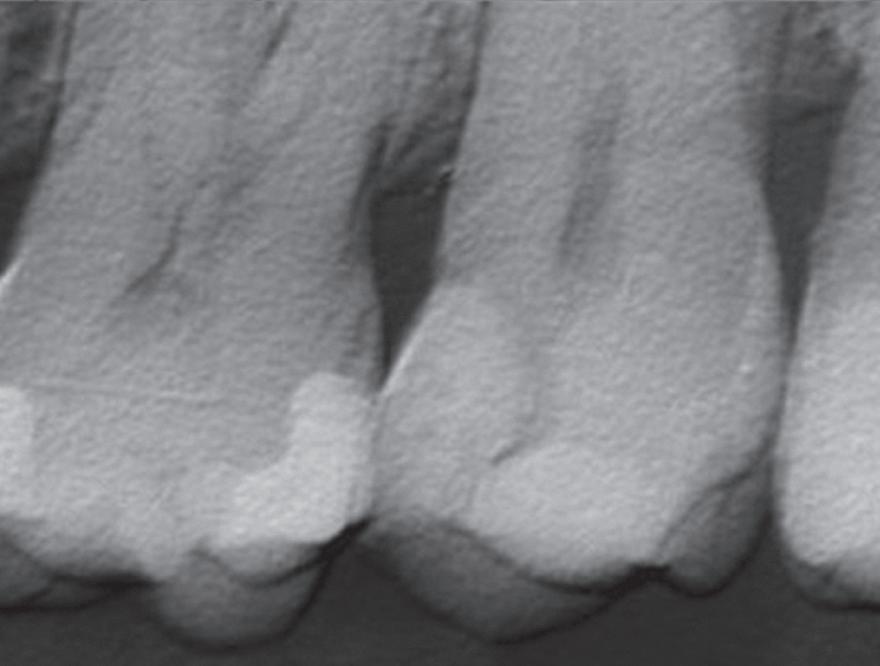

Clear radiographs are essential to accurate diagnosis and are a special test that dentists per form regularly many times throughout the day. Following the ALARA principle, we want to ensure we take a minimal number of radio graphs to ensure low radiation dosage so to repeat radiographs due to operator error should be avoided. The use of film holders allow the clinician to visualise how the radiographs should be taken to optimise the clarity of the image and ensure the diagnostic value of the image. Hawe Solutions x-ray film holders...

Figure 1: Radiographic Image of implants do not demonstrate bone loss due to the bisecting angle of the radiograph taken.

Figure 2: Radiographic image in a paralleling technique of implants dem onstrate moderate peri-implantitis with bone loss that will necessitate treatment.

• Allow exact posi tioning of the film or phosphor plate relative to the tooth - no bending and thus no distortion;

• Require no guesswork - exclusive, automatic reliance on the extraoral aiming and centring device;

• Deliver semi-reproducible images (quasi standardisation)the use of film holders allows some sense of reproducibility for assessment over time; and

• Produce optimally clear radiographs.